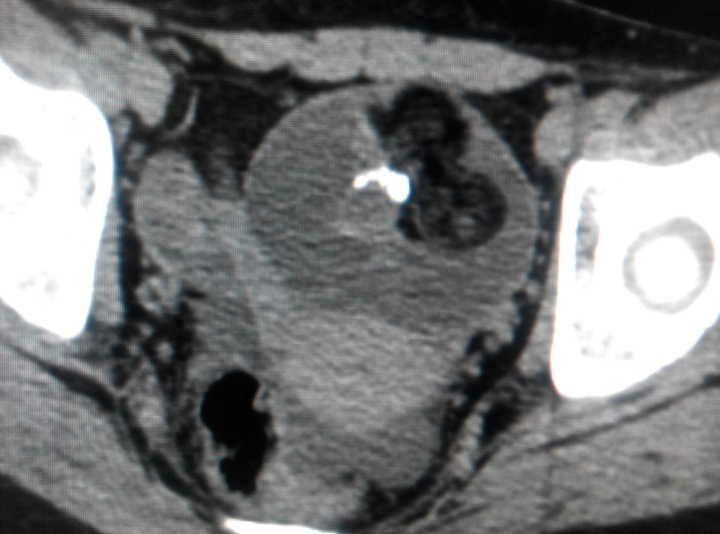

患者,女性,发现右下腹包块10个月。患者于10个月前体检时发现右下腹包块,当时未予注意,现为求进一步治疗收入我科。16/12我院门诊阴道彩超示:子宫右附件区囊实性占位,右卵巢畸胎瘤可能性大。(畸胎瘤的成分复杂,可以有脂肪、钙化等,所以CT有脂肪密度,密度不均,如果有钙化是成熟畸胎瘤。成熟畸胎瘤绝大部分为囊性,又名囊性畸胎瘤,占畸胎瘤的97%,可发生于任何年龄,有80%~90%的患者为生育期妇女。畸胎瘤病理类型各异,有壁立性结节征,面团征,脂液分层征,瀑布征,星花征,多囊征,杂乱结构征,线条征等等)该患者彩超图如下,可以看到子宫右上方有一大小约54*48mm的低回声囊实性包块,囊内有一高回声水平界线,上层为液性无回声区(黑色部分),亦可见液内悬浮少量光点,下层为脂类物(灰色部分),呈分布均匀的密集细小光点,这畸胎瘤特征之一的脂液分层。因为患者已经打算做手术的了,所以没有做盆腔CT,下面这三张盆腔CT是我叫白开水给我找的,我挺不厚道的借用了他的图,有怪莫怪,有怪莫怪哈。。。。。。患者今天做了手术,切除物已经送病检了,但是病检估计要一周才可以回来,到时追踪下病检再补充好了。。。